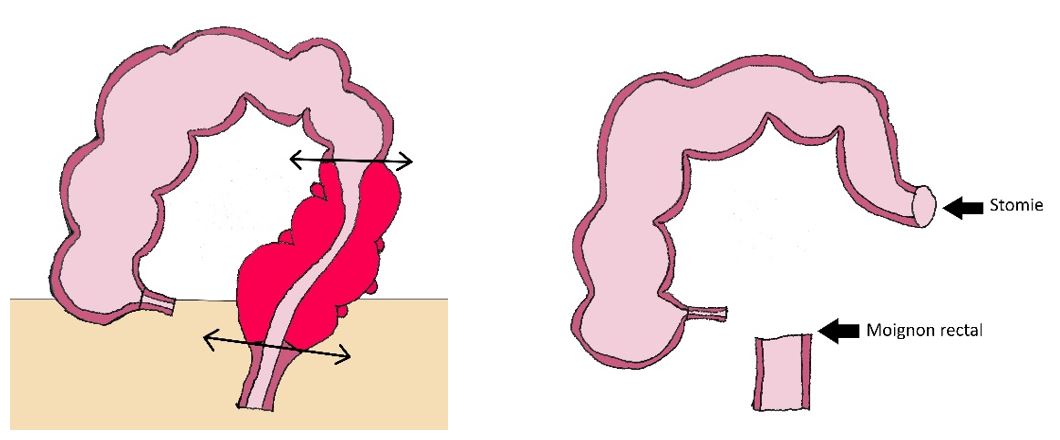

En cas de péritonite (infection généralisée du ventre), dont le diagnostic est fait à l’examen clinique et sur le scanner, une chirurgie en urgence doit être réalisée. Elle consiste à retirer le sigmoïde sur lequel se trouvent les diverticules. Le plus souvent il est nécessaire de réaliser une colostomie (poche permettant l’évacuation des selles) de façon temporaire car une couture sur le colon ne cicatrise pas dans l’infection. C’est ce que l’on appelle l’intervention de Hartmann.

En cas d’abcès ou de sigmoïdite « perforée bouchée » n’évoluant pas de façon favorable (augmentation des douleurs, persistance de fièvre, aggravation du bilan sanguin), une chirurgie est également nécessaire. La chirurgie réalisée est la même que celle réalisée pour péritonite.

Lors de la réalisation d’une intervention de Hartmann, la stomie peut être fermée (rétablissement de la continuité) 3 mois après la chirurgie initiale. L’opération consiste alors à réaliser une couture entre la stomie et le rectum laissé dans le ventre.